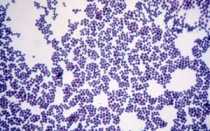

Коагулазонегативные стафилококки: что это, особенности и лечение В природе существуют микроорганизмы, способные вырабатывать токсины, нарушающие жизнедеятельность клеток живого организма, разрушительно...